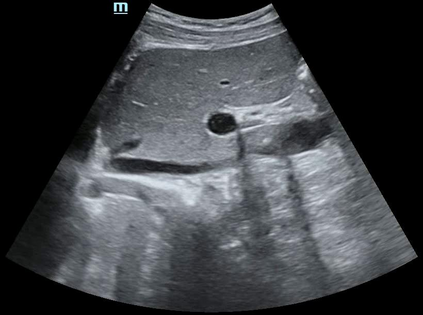

Most deep neural networks (DNNs) based ultrasound (US) medical image analysis models use pretrained backbones (e.g., ImageNet) for better model generalization. However, the domain gap between natural and medical images causes an inevitable performance bottleneck. To alleviate this problem, an US dataset named US-4 is constructed for direct pretraining on the same domain. It contains over 23,000 images from four US video sub-datasets. To learn robust features from US-4, we propose an US semi-supervised contrastive learning method, named USCL, for pretraining. In order to avoid high similarities between negative pairs as well as mine abundant visual features from limited US videos, USCL adopts a sample pair generation method to enrich the feature involved in a single step of contrastive optimization. Extensive experiments on several downstream tasks show the superiority of USCL pretraining against ImageNet pretraining and other state-of-the-art (SOTA) pretraining approaches. In particular, USCL pretrained backbone achieves fine-tuning accuracy of over 94% on POCUS dataset, which is 10% higher than 84% of the ImageNet pretrained model. The source codes of this work are available at https://github.com/983632847/USCL.